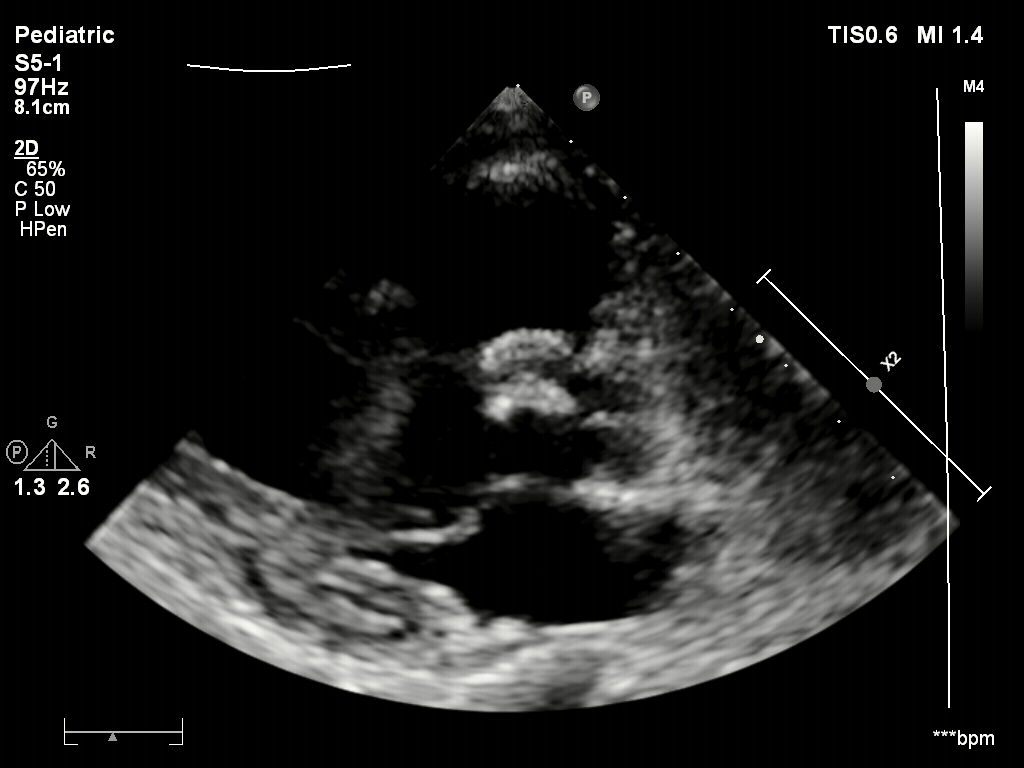

超声下可见右盘面展开

超声下确认封堵器位置正确

骑跨于室间隔两侧

释放封堵器后,超声下观察封堵器形态良好

无残余分流,封堵成功

封堵器稳定夹持在室间隔两侧,无残余分流